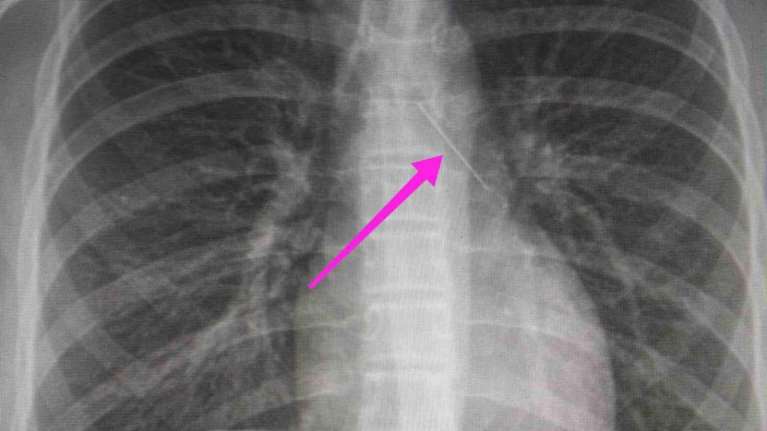

Θεσσαλονίκη: Ανήλικη κατάπιε καρφίτσα- Βρέθηκε "σφηνωμένη" στον δεξιό κύριο βρόγχο

Η ανήλικη υπεβλήθη σε βρογχοσκόπηση και διαπιστώθηκε η μετακίνηση και ενσφήνωση της καρφίτσας στον δεξιό κύριο βρόγχο